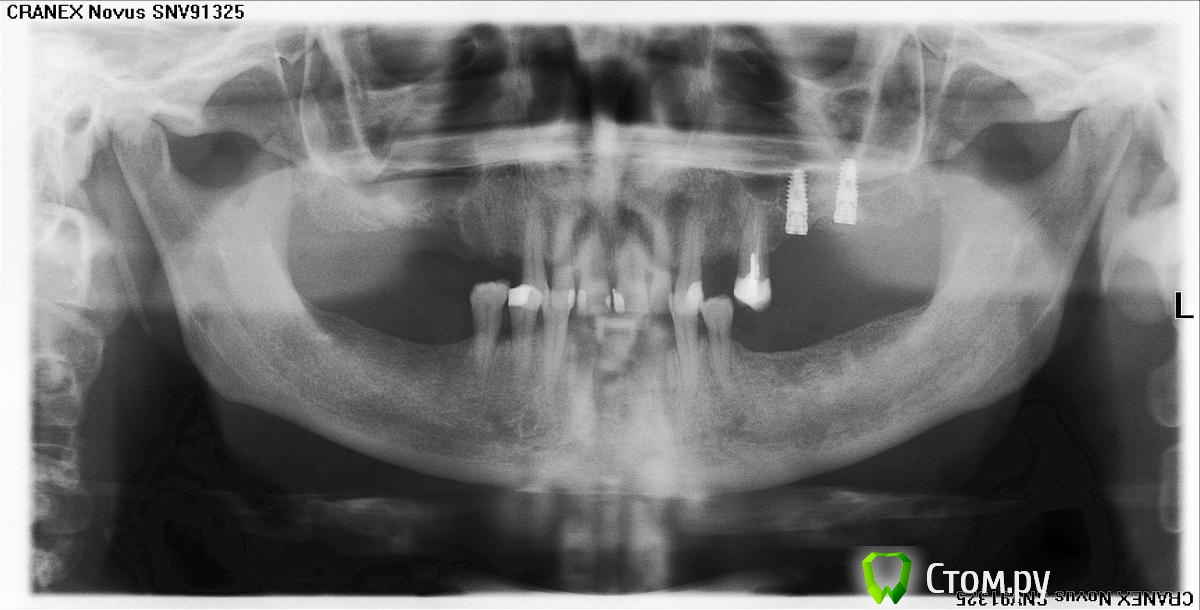

Stomatolog07 Опубликовано 8 декабря, 2013 Поделиться Опубликовано 8 декабря, 2013 Между септой и имплантом незаполненное графтом пространство. Кто что думает? Какие еще замечания будут? Ссылка на комментарий

АнтонТЛТ Опубликовано 8 декабря, 2013 Поделиться Опубликовано 8 декабря, 2013 какие варианты исхода еще могут быть? (Мало опыта) Спасибо!1) Между имплантом и септой кровяной сгусток, появится кость и имплантат нормально интегрируется.2) Имплантат порвал шнайдерову мембрану, интегрируется в малый объем кости и этого хватит.3) Имплантат порвал шнайдерову мембрану, плохо интегрируется и выкрутится на этапе установки формирователя. 2 Ссылка на комментарий

Stomatolog07 Опубликовано 8 декабря, 2013 Автор Поделиться Опубликовано 8 декабря, 2013 1) Между имплантом и септой кровяной сгусток, появится кость и имплантат нормально интегрируется.2) Имплантат порвал шнайдерову мембрану, интегрируется в малый объем кости и этого хватит.3) Имплантат порвал шнайдерову мембрану, плохо интегрируется и выкрутится на этапе установки формирователя.Спасибо! Вроде не прорвал. После установки иплантов графт докладывал, вроде не мигрировал выше. Ссылка на комментарий